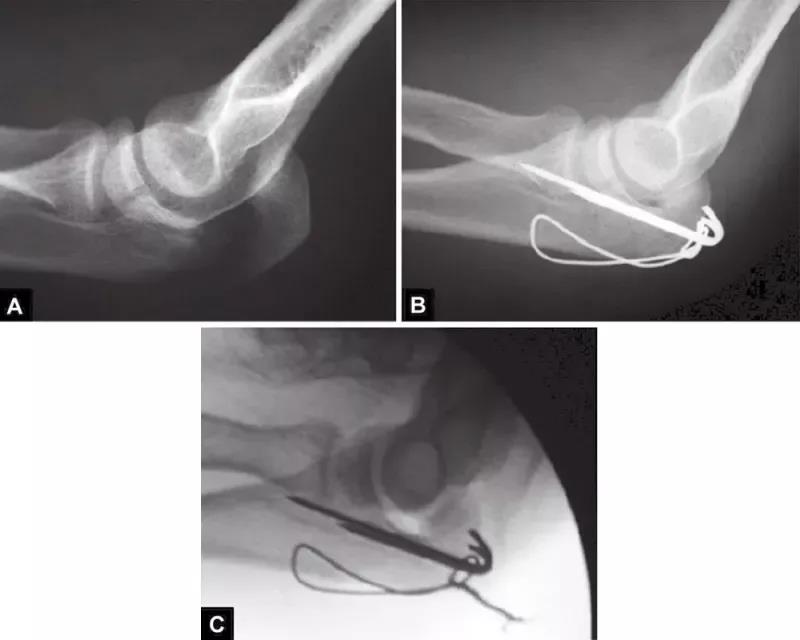

图1A~C(A)关节压缩骨折不易觉察,有经验的医生会注意到从冠状突到鹰嘴尖的关节间隙增宽而得出诊断;(B)如果没有的观察力,医生甚至会在术中X线片检查中都漏诊明显的压缩骨折。医生的注意力完全集中在检查植入物的位置上,因此容易忽略关节不一致;(C)术后摄片显示压缩骨折未复位